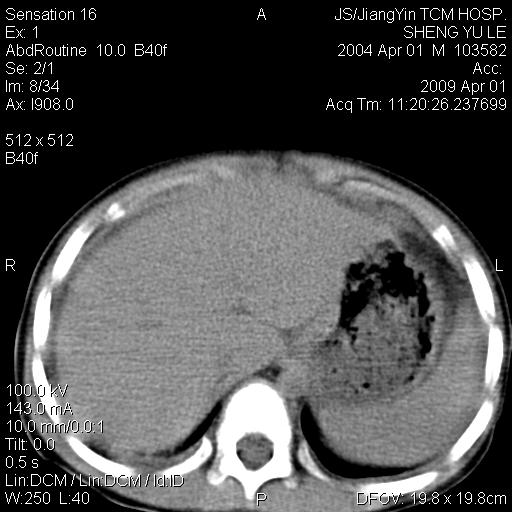

m,5岁。尿痛尿频数天。既往无病史。ct平扫腹盆腔积液。膀胱壁明显增厚。另可见心包增厚。wbc5万,骨髓穿等结果。请指教。

膀胱影像表现结合临床应该是急性膀胱炎症,但为什么有腹水呢?双肾输尿管无扩张,泌尿系压力应该不大不至于引起尿外渗,应该是腹膜感染引起的,但楼主没有提及相关症状,腹膜及膀胱结核?患者白细胞5万(结核不至于这么高啊),脾脏增大,是不是有白血病?进一步检查。。